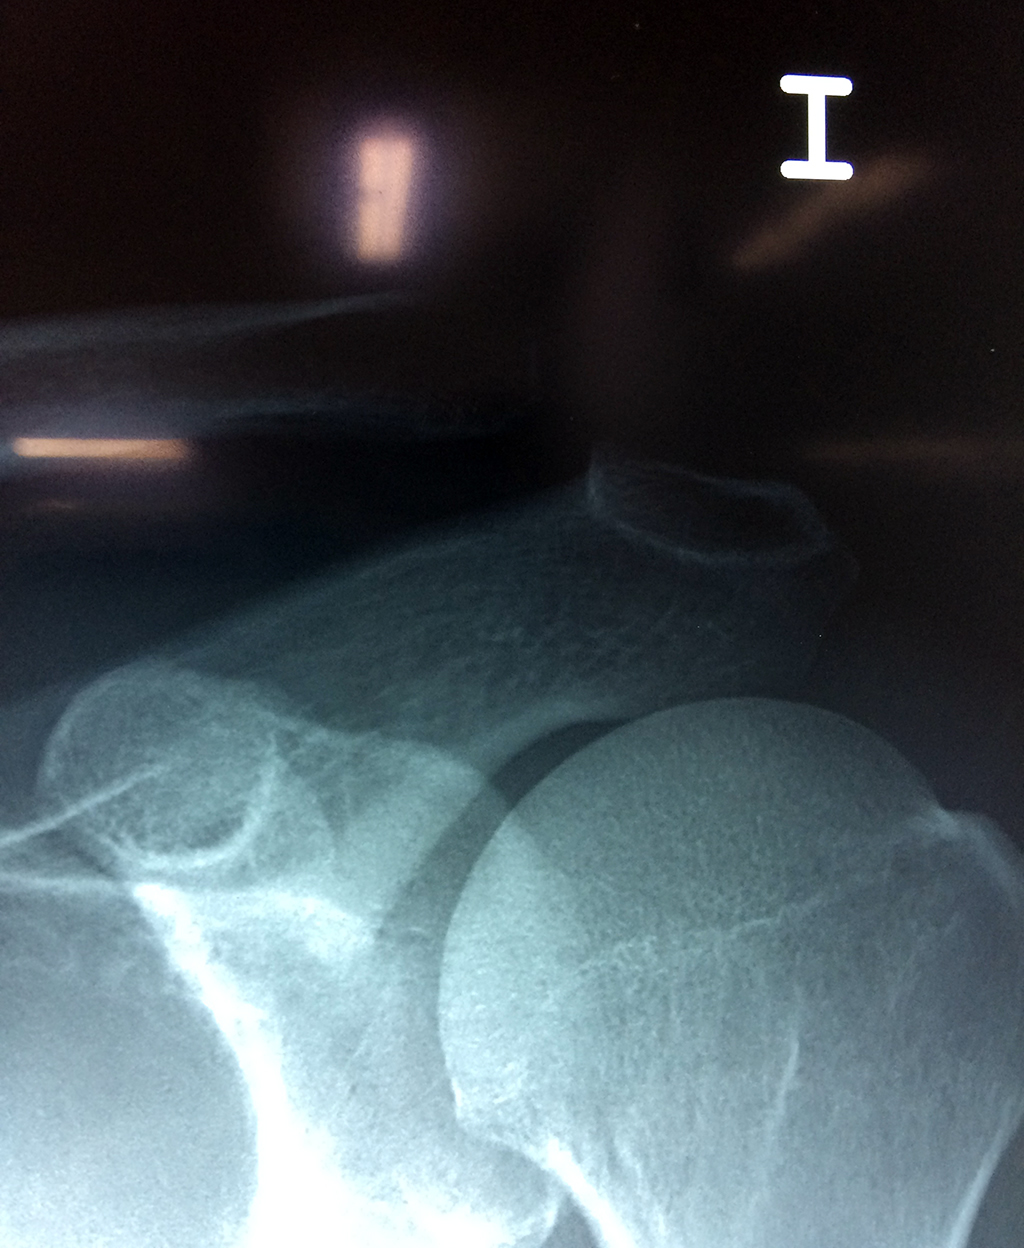

Húmero - Clavícula

La clavícula es un hueso largo, con forma de "S" itálica, situado en la parte anterosuperior del tórax. Junto con la escápula forman la cintura escapular. Se puede palpar por toda su longitud y se extiende del esternón al acromion de la escápula, siguiendo una dirección oblicua lateral y posterior.